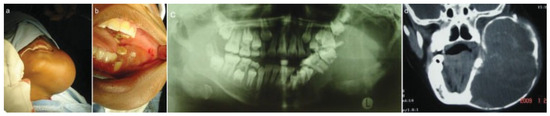

A 12-year-old girl presented to a maxillofacial and oral surgery practice with swelling of her left mandible (Figure 1a). The swelling was present for several months and progressively increased in size. The large mass made mastication increasingly difficult. Clinical examination revealed a large extraoral swelling extending from the posterior border of the ramus to about the lower left canine region anteriorly. Intraorally, there was an expansile lesion of the left side of the mandible with mobile displaced teeth (Figure 1b). The mass moved on movement of the mandible. There was no bruit on auscultation. Routine hematologic studies included full blood count, urea and electrolyte studies, activated partial thromboplastin time, random glucose and liver function tests. These were found to be within normal limits. HIV serology was nonreactive. There was no further contributory medical history.

Figure 1. (a) Preoperative extraoral view. (b) Preoperative intraoral view showing expansion of alveolus. (c) Preoperative orthopantomograph. (d) Computed tomography scan.

Imaging studies included chest radiographs, an orthopantomograph, posteroanterior mandibular radio-graph, computed tomography (CT), and CT angiogram (Figure 1c,d and Figure 2a–c). The chest radiographs were normal. The orthopantomograph showed an expansile lesion of the left side of the mandible involving the ramus and body with associated displaced and floating teeth. CT studies included 1.5 × 3-mm overlapping axial cuts, 5 × 5-mm coronal cuts through the same region, and 5 × 5-mm spiral axial scans through the mandible after contrast administration. Imaging studies showed a large expansile multilocular cystic mass involving the left mandible. The mass measured 8 × 9 cm and 152 to 158 Hounsfield units, which was diagnostically suggestive of a vascular lesion radiologically. There were septae and some enhancing soft tissue components within the mass. The lesion extended to the nasopharynx and oral cavity medially, to the base of the skull superiorly, and to the parotid and carotid spaces posteriorly. There was no intracranial involvement. The patient was booked for incisional biopsy. Prior aspiration of the lesion was positive for blood, which appeared to be of a high-flow nature. To avoid the possibility of uncontrollable intra-operative bleeding, the procedure was abandoned. Based on the imaging studies, a provisional diagnosis of an ABC was made. Attempted shrinkage of the lesion was considered with the use of embolization. The patient was therefore referred to an interventional radiologist for possible embolization of the lesion. Embolization of the internal maxillary artery on the left side was done with 100- to 300- as well as 300- to 500-size contour particles. A silicone SL14 catheter (Jet Medical South Africa, Gauteng, Cape Town, KZN, South Africa) with a Silver Speed guide wire (Micra Therapentics, Inc., Irvine, CA) was used to do superselective embolization of the feeding vessels to the tumor. An angiogram done at this stage showed a highly vascular mass in the left mandible. The patient was unable to keep to the regular appointments due to financial constraints and therefore presented herself 3 months after embolization. The lesion was found to have increased in size. New CT scans confirmed that the lesion had increased in size and was still highly vascular. A decision was taken to surgically remove the lesion after ligation of the ECA with immediate reconstruction of the mandible. Postresection reconstruction was preplanned using stereolithographic models to achieve maximum preoperative symmetry and function.